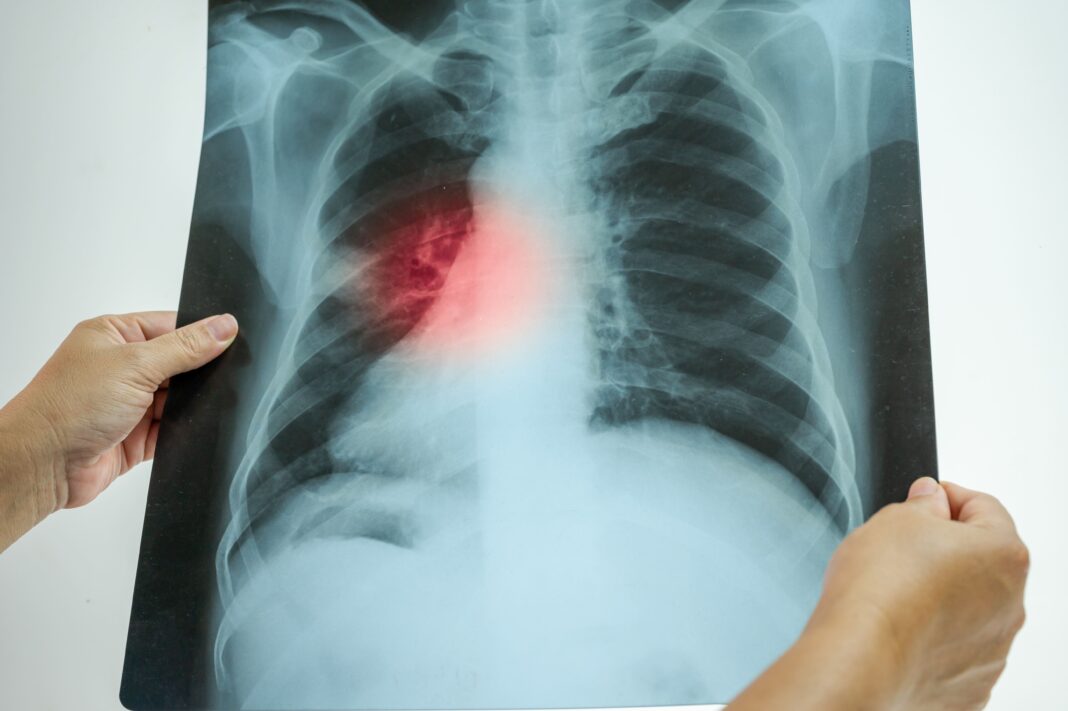

Gruźlica atakuje głównie płuca, ale także węzły chłonne, kości czy mózg, powodując zapalenie opon mózgowo-rdzeniowych. Objawy bywają mylące, ponieważ często przypominają grypę. Do najczęstszych należą kaszel trwający ponad trzy tygodnie, gorączka, nocne poty, utrata apetytu oraz spadek masy ciała.